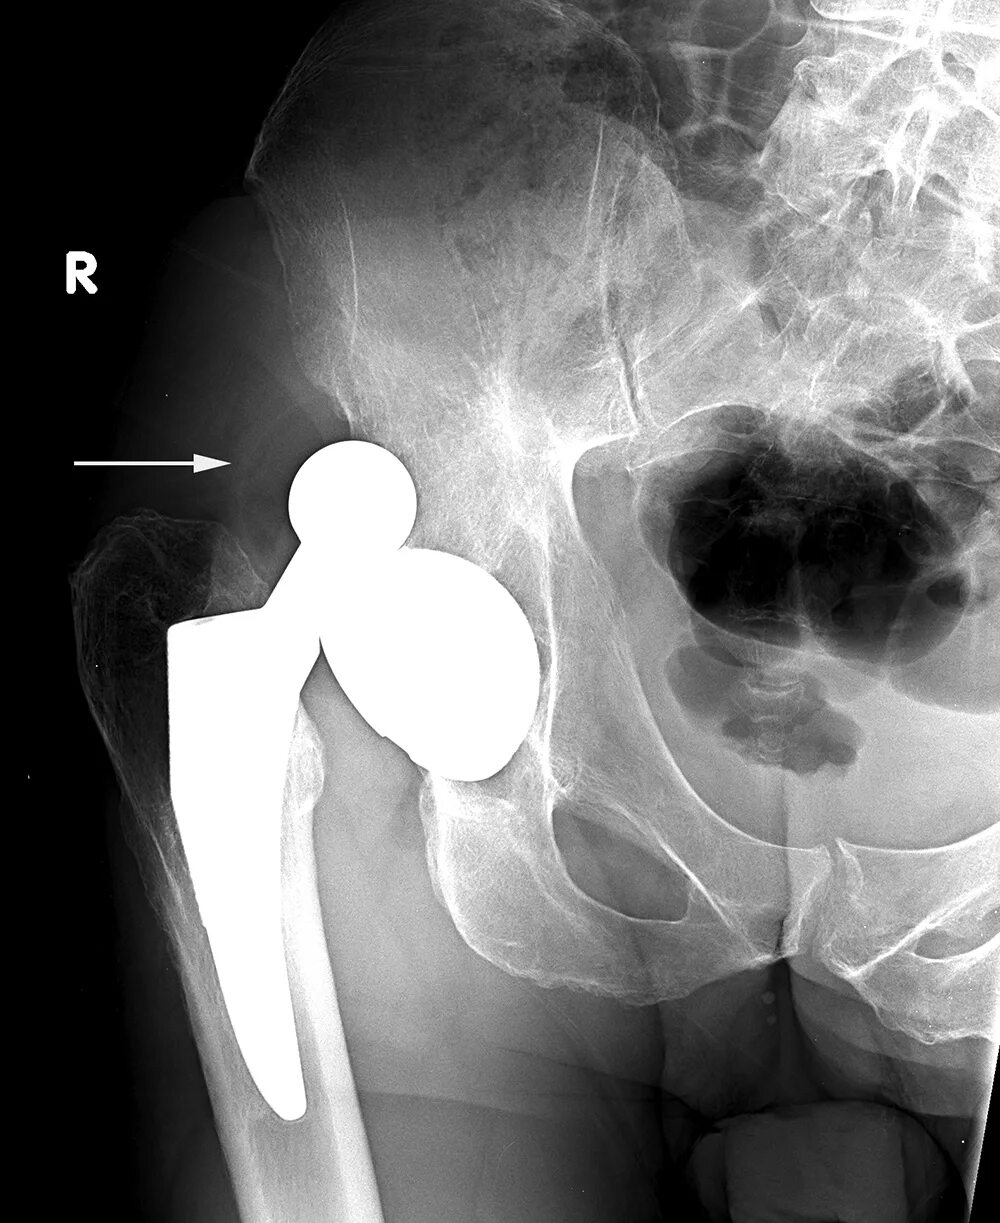

Рентген тазобедренный в двух проекциях